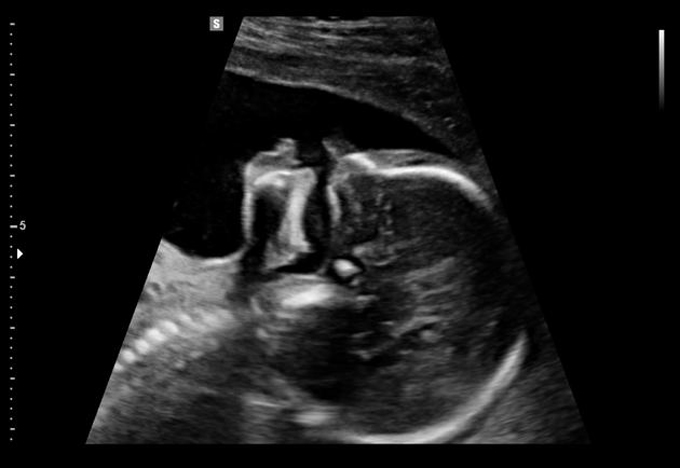

Siêu âm ba tháng cuối sử dụng đầu dò có tần số 3,5 MHz, độ đâm xuyên tốt nhưng hình ảnh độ phân giải không bằng siêu âm đường âm đạo trong những tháng đầu. Siêu âm đường bụng 3 tháng cuối thông thường để khảo sát thai nhi về các thông số: Đường kính lưỡng đỉnh, đường kính vùng bụng, cân nặng thai, lượng nước ối,...

Hình ảnh thai sứt môi - hở hàm ếch phát hiện được trên siêu âm

Hình ảnh thu được trên màn hình siêu âm cho phép bác sĩ Sản khoa “nhìn vào” buồng ối của mẹ, đánh giá trung thực cấu trúc những cơ quan quan trọng, cấu trúc xương cũng như não bộ của thai nhi.

Các loại dị tật siêu âm có thể phát hiện trong 3 tháng cuối: Sứt môi hở hàm ếch, chi ngắn, não úng thủy, tim bẩm sinh, thoát vị hoành, bất thường bộ phận sinh dục,…

Mức độ chính xác: Giao động 50 - 70% tùy kinh nghiệm của người siêu âm.